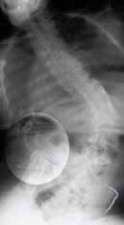

Chapter 63 Hemivertebra Excision Daniel J. Hedequist and John B. Emans DEFINITION A hemivertebra is a congeni…